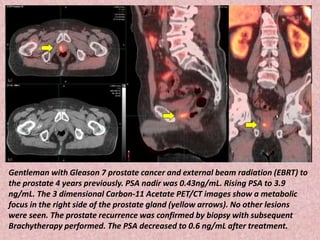

Gentleman with Gleason 7 prostate cancer and external beam radiation (EBRT) to

the prostate 4 years previously. PSA nadir was 0.43ng/mL. Rising PSA to 3.9

ng/mL. The 3 dimensional Carbon-11 Acetate PET/CT images show a metabolic

focus in the right side of the prostate gland (yellow arrows). No other lesions

were seen. The prostate recurrence was confirmed by biopsy with subsequent

Brachytherapy performed. The PSA decreased to 0.6 ng/mL after treatment.